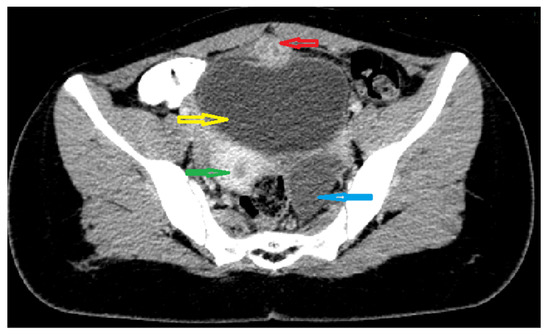

The abdominal ultrasound (US) discovered a 28/21 mm hypoechogenic round tumor in the midline of the hypogastric region, anterosuperior to the bladder and posterior to the abdominal wall, with diffuse mural thickening. The uterus and both ovaries appeared to be normal. We decided to perform a pelvic MRI which showed a 16/18/32 mm inhomogeneous nodular lesion, apparently on the urachal tract; the bladder was in repletion, with mural thickening of the anterosuperior wall. The left ovary presented a 41/34 mm cyst, considered as a hemorrhagic corpus luteum (Figure 1).

Figure 1. Pelvic MRI image: Sagittal T2-weighted yellow arrow: left ovarian cyst; green arrow: supposed urachal cyst; red arrow: urinary bladder.